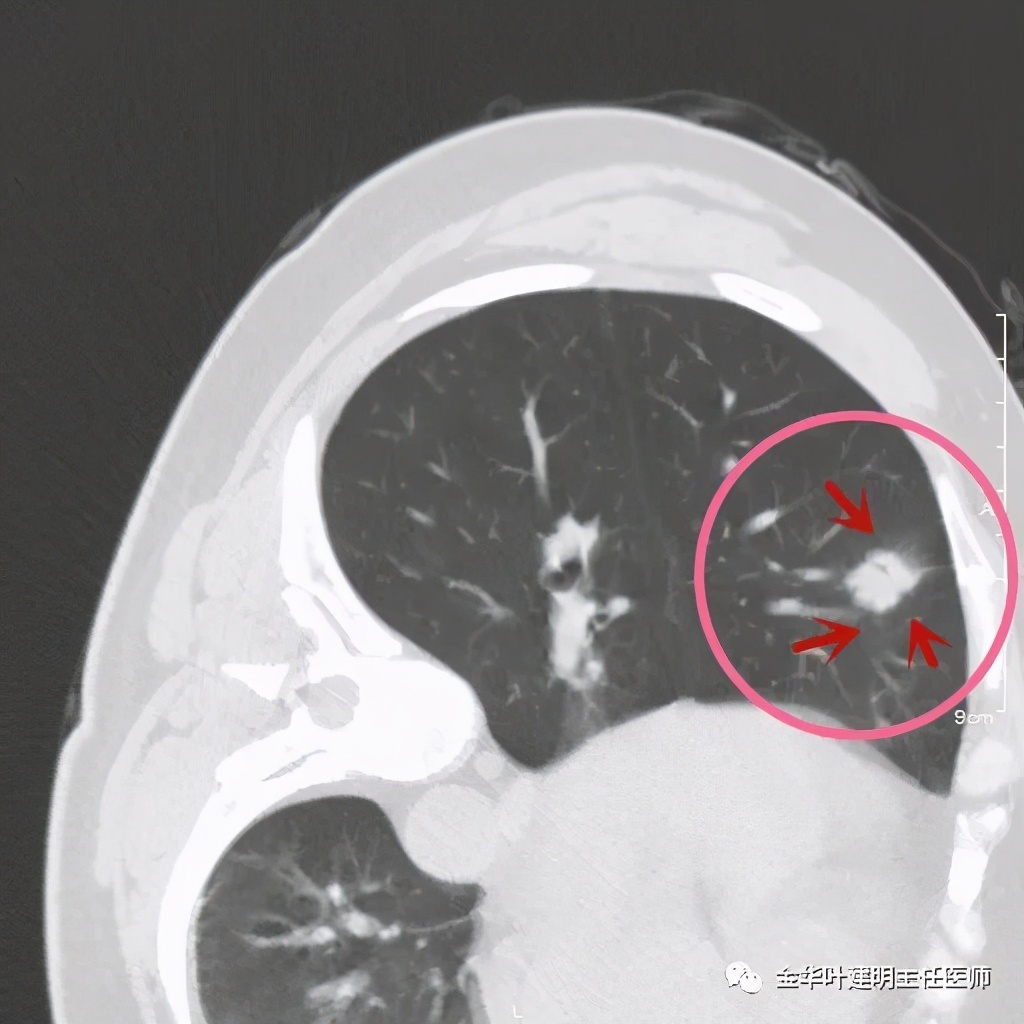

六、神经内分泌癌(此例为不典型类癌,小细胞癌以后再总结):

影像特征:不典型类癌一般圆形生长,实性,边缘比较光滑,但硬度不够。侵蚀力也不够。就像这例,我们发现其与肺动脉接触的地方,居然无法推压血管,反而肿瘤被血管占据了其生长的位置,在支气管内,肿瘤也是对支气管壁没有造成明显的破坏。也就是说 圆形边清较软、侵蚀力弱的实性结节 要考虑类癌的可能性。